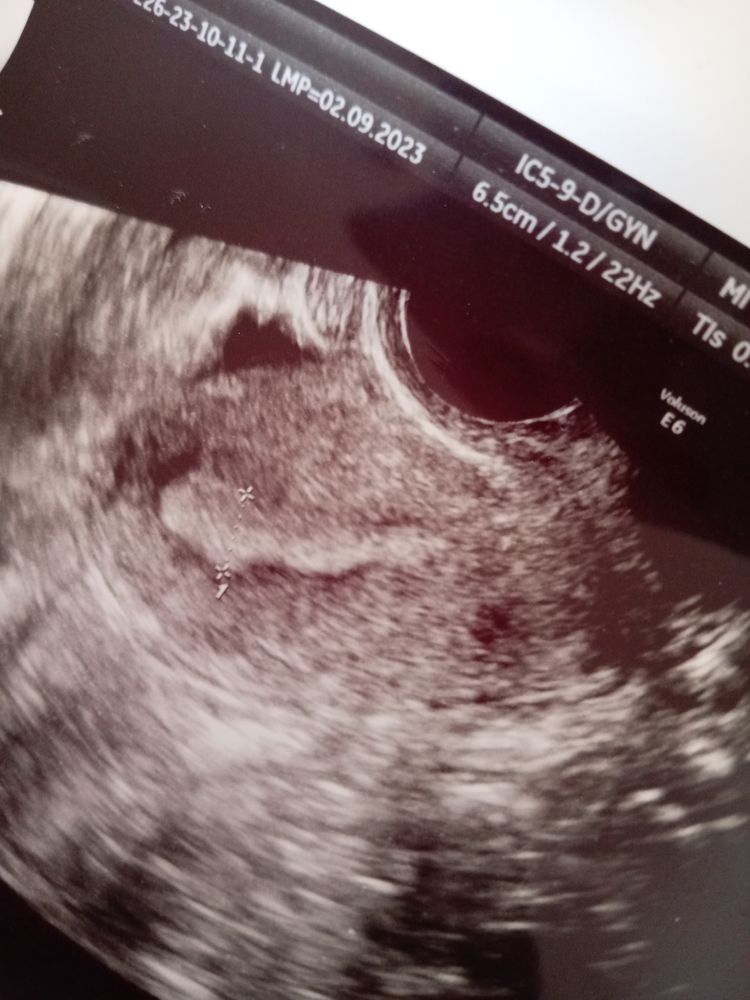

У меня всегда ростут по два фолекула одновремена. Цисти в размерах 1) 31.1х29мм 2)24х15мм. Ендометрий 8.1мм для меня хорошый , у меня всегда 5-6мм. я спросила может кисти жт она ответила вратли 😭😭😭 грудь болит вобласть подмышек ужасно даже тогда когда я не трогаю, и чешится. Может ошибка? она отправила к врачу надо лечит кисти и отпустила.

teko xulordava, мне врачи сказали и узистка. Но у меня кисты большие 81*52 и внутри 40мм. Сказали если до 30мм, то это жёлтое тело, его почему-то называют кисты.

Анастасия эко, уменя один 31мм второй 24мм 🙈 все симтомы О яб и бол в яичнике и по тесту и по бт а она мне говорит,что не было. Так сложно отлечить фолекуларную кисту и жт?